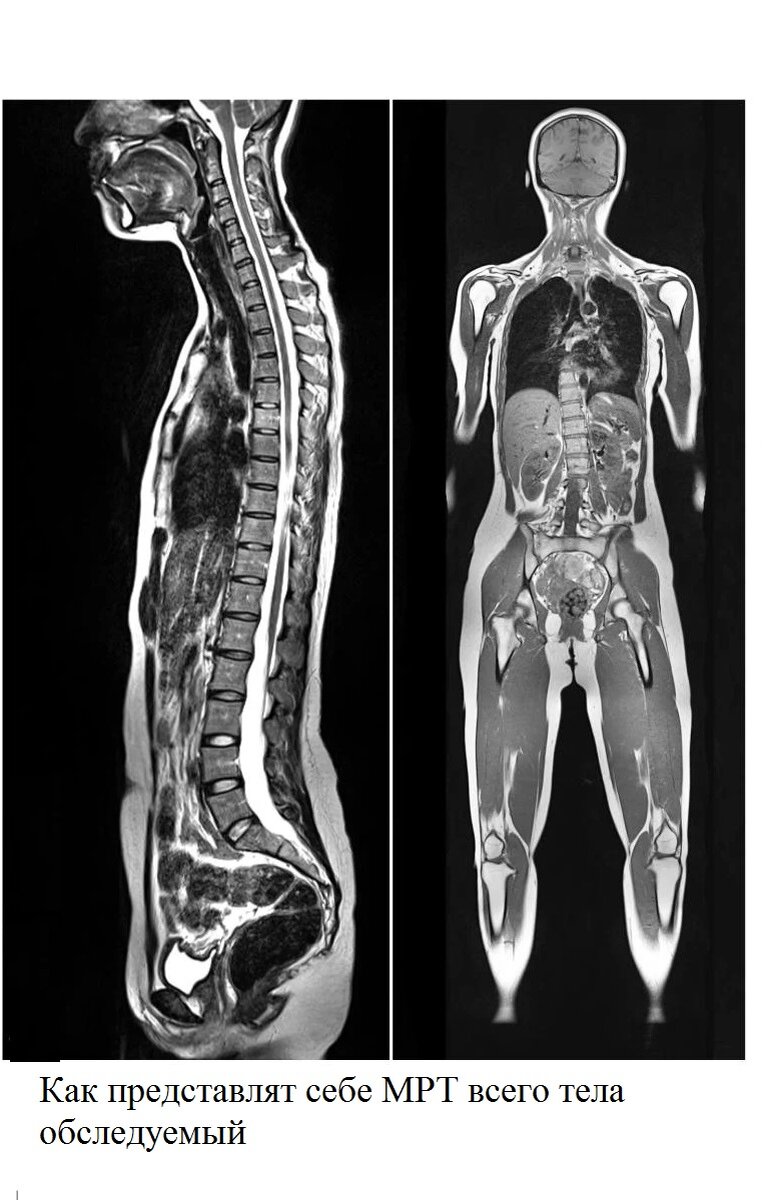

Все больше знаменитей в социальных сетях рассказывают о преимуществах МРТ всего тела, как о профилактическом медицинском обследовании, главным образом с целью поиска онкологических заболеваний. Выкладывают фото в социальных сетях, которые собирают много лайков и похвальных комментариев, в духе, - Какие Вы молодцы, - следите за свои здоровьем. А вот многие врачи обеспокоены такой тенденцией. В наше время мы слышим о МРТ сканировании всего тела все чаще. Может ли МРТ всего тела качественно проверить все органы и ткани? Выявить такое заболевание, как рак на ранней стадии? Ответы, на эти вопросы будут не однозначные. Там много деталей, важных деталей в которых сейчас будем разбираться. Обратился как-то давний знакомый Михаил, говорит, - хочу МРТ всего тела пройти, что бы все проверить полностью. Мне показалось это странным. Я знал его уже много лет, и он ни разу ко мне не обращался, а тут решил провериться, да еще и все сразу. Я спросил, - что вообще беспокоит? Он ответил, - особо ничего,

Все больше знаменитей в социальных сетях рассказывают о преимуществах МРТ всего тела, как о профилактическом медицинском обследовании, главным образом с целью поиска онкологических заболеваний. Выкладывают фото в социальных сетях, которые собирают много лайков и похвальных комментариев, в духе, - Какие Вы молодцы, - следите за свои здоровьем. А вот многие врачи обеспокоены такой тенденцией.